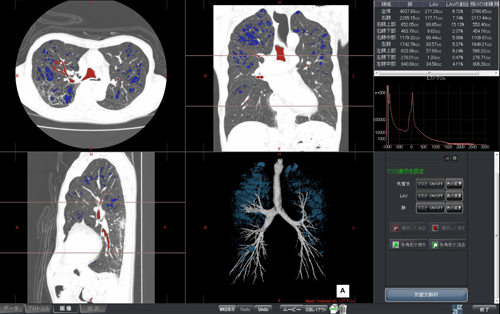

気管支の壁厚,WA%,TD比を自動で算出し,気管支の観察や肺気腫のボリューム解析が可能です。わかりやすい操作メニュー,ワンクリックで任意の気管支のパスの抽出や肺気腫の体積の算出等も行える等,シンプルな操作で目的まで到達することができます。ボリューム解析では肺と肺気腫の面積/体積の計測および各領域における肺気腫のリストを表示します。

図3 CT肺野・気管支測定